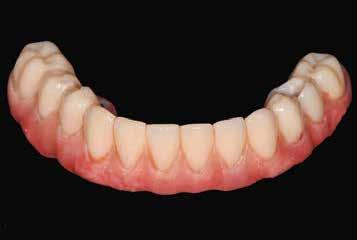

Hagyományos teljes fogsor hatékony átalakítása

A digitális technológiákhoz való hozzáférést az anyagi és időkorlátok akadályozhatják, valamint az ilyen technológiákhoz kapcsolódó meredek tanulási görbe.8,9 A közelmúltban a digitális munkafolyamatok elérhetővé váltak egy kihelyezett szolgáltatás részeként: Smile in a Box (Straumann). Ez segíthet a hagyományos munkafolyamatokat használó szakembereknek, hogy könnyen élvezhessék a digitális technológiák előnyeit anélkül, hogy először le kellene küzdeniük az első hozzáféréssel járó akadályokat. Ez az esettanulmány egy hagyományos teljes fogsor sikeres azonnali átalakítását írja le azonnali teljes ívű restaurációvá a Smile in a Box által biztosított kiszervezett, teljesen digitális munkafolyamat alkalmazásával. A Straumann Pro Arch protokoll alkalmazása a Smile in a Box funkcióval kombinálva lehetővé tette számunkra, hogy könnyen hozzáférhessünk egy teljesen digitális munkafolyamathoz, amely hatékonyan integrálható a hagyományos protetikai munkafolyamatunkba, továbbá rendkívül kielégítő klinikai eredményt biztosít.

A hagyományos teljes kivehető fogpótlási technikákkal a kezelési stratégia a felső és alsó állcsont kapcsolatának és az okkluzális vertikális dimenzió és a fog helyzetének meghatározását foglalta magában, majd az alsó rögzített restauráció előállításához ezeket használták fel referenciákként (3. ábra) 11